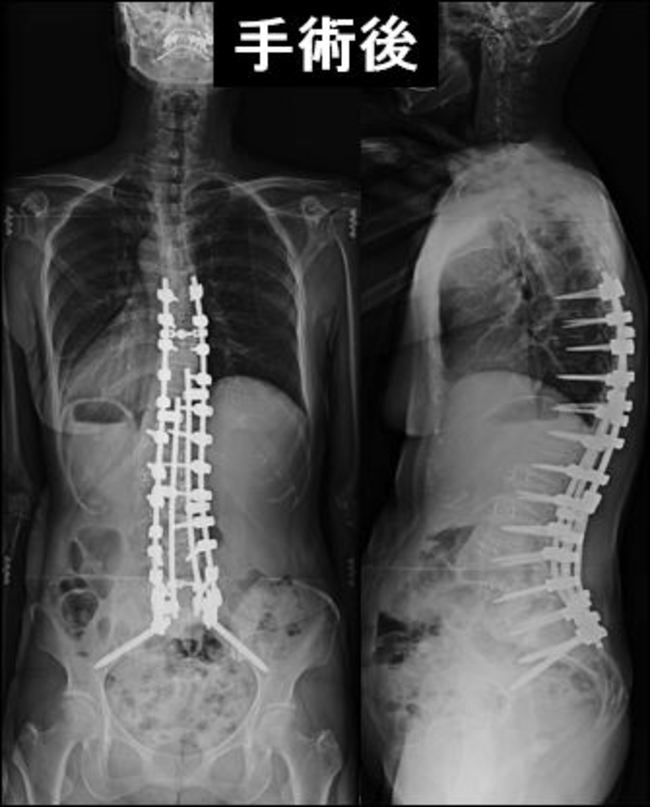

特発性側弯症

未だにその原因は不明ですが、多くの場合思春期に発症・悪化します。 約9割は女の子に発症します。「せぼね」(脊柱)が、ねじれを伴って曲がっています。このため肩の高さやウエストラインの高さに差があらわれ、身体が左右非対称性になってしまいます。お辞儀をしたときの背中や腰の高さにも左右差が出ます。多くは思春期に進行します。40°近くになると服の上からも目立ってきます。

<側彎症の治療>

成長終了前で40°未満であれば、装具療法で進行を予防出来ます。ただしこの場合、長時間、長期間の装着が必要です。体操など、他の治療法の効果は科学的に証明されていません。 40°を越えてしまった場合には、美容面と進行予防の目的で手術を行います。